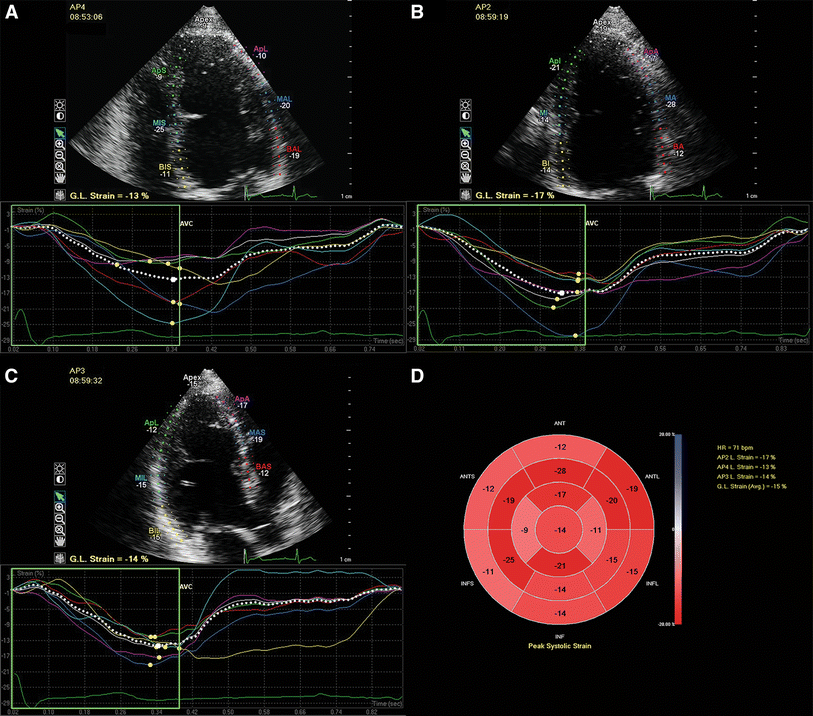

Example of left ventricular longitudinal strain measurements in a patient with repaired aortic coarctation. The LV was traced in the apical four-, two-, and three-chamber views at end-diastole. The walls were automatically divided into seven segments at each view and the global longitudinal strain at each view was calculated (a–c). The segmental strain measurements were plotted in a bull’s eye and the left ventricular global longitudinal strain based on all three apical views was calculated (d). AP2 apical two-chamber view, AP3 apical three-chamber view, AP4 apical four-chamber view, GL global longitudinal